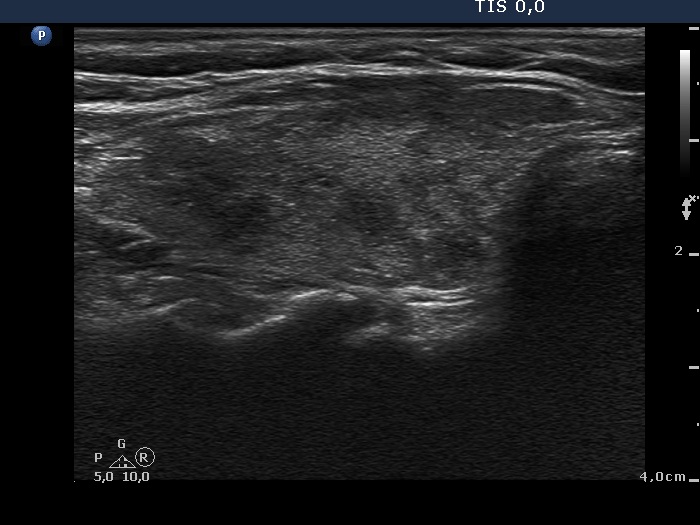

Ultrasonography: A diffusely hypoechogenic thyroid was found with multiple more hypoechogenic lesions. None of them corresponded to a nodule. The vascularization was increased.Daily 20 mg methimazole was administered and repeat radioiodine therapy was advised after reaching the euthyroid state.

Ultrasonography: The extent of hypoechogenic areas have decreased, otherwise the pattern was unchanged.We suggested again a repeat radioiodine therapy.

Ultrasonography: The pattern was the same.

Ultrasonography: unchanged.Cytology was performed from the hypoechogenic area in the upper part of the right thyroid.

Comment. It is worth analyzing the echo pattern of the thyroid. The small hypoechogenic area in the right lobe changed neither in size nor is shape nor in vascularization over 11 months.